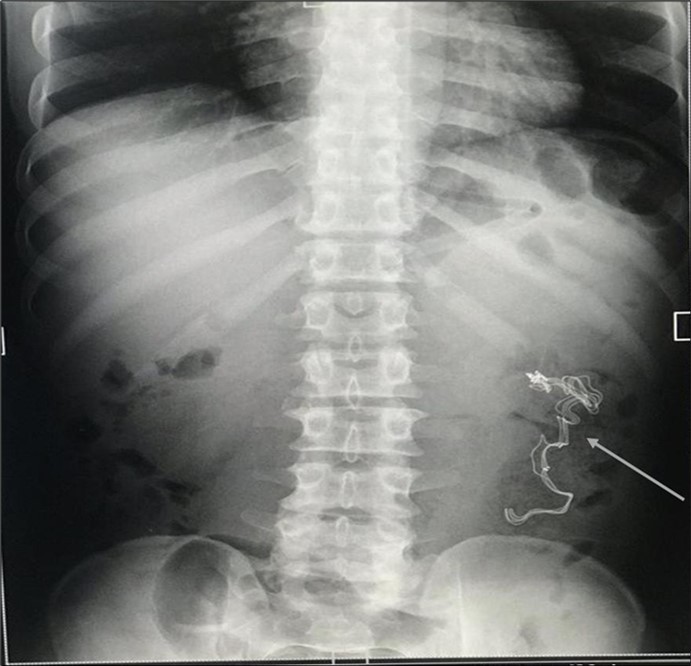

An impression of an intestinal obstruction due to postoperative adhesions was made. An abdominal X-ray done showed no obvious signs of bowel dilatation but an ill-defined opacification in the area of the left lumbar region (Figure 1). An ultrasonography done showed an echogenic mass in the left iliac region measuring about 4.1cm in diameter. There was no flow on colour doppler interrogation (Figure 2). At this point a diagnosis of foreign body was queried. The patient was counselled and prepared for exploratory laparotomy.

Figure 1.Erect abdominal X-Ray showing an ill-defined opacification in the left lumbar region (arrowed).

Erect abdominal X-Ray showing an ill-defined opacification in the left lumbar region (arrowed).